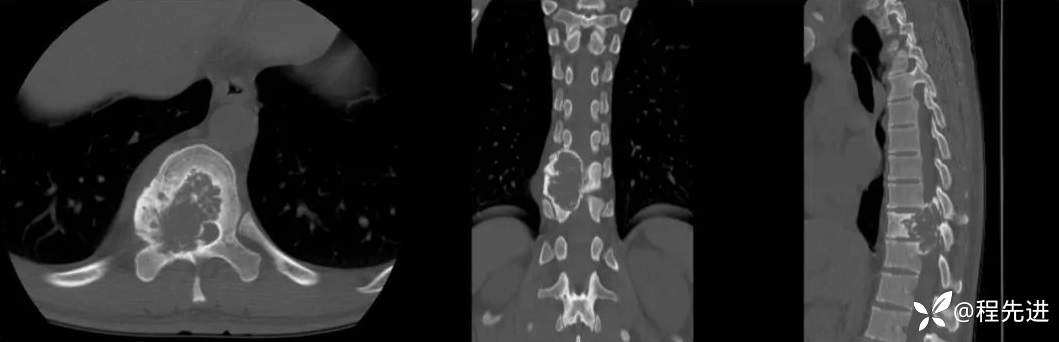

CT: